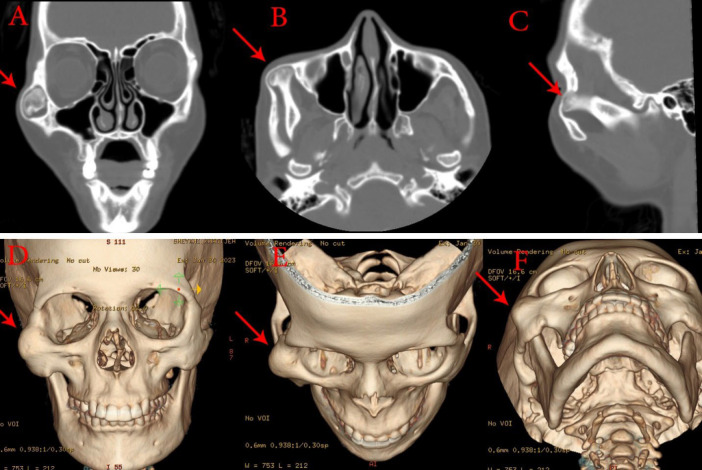

Osteochondroma, the most common benign tumor in the axial and appendicular skeleton, presents a unique challenge when encountered in the craniofacial region. We report a rare case of a 35-year-old female with a massive osteochondroma located on the mandibular coronoid process, resulting in a 20-year history of progressive mouth opening limitation, facial asymmetry, and zygomatic deformity. Comprehensive diagnostic procedures, including panoramic radiography and computed tomography (CT) imaging, were employed to accurately assess the extent of the lesion. This case highlights the importance of CT scans and three-dimensional reconstructions in confirming the diagnosis, particularly when panoramic radiographs exhibit limitations. The patient underwent a successful extraoral approach for coronoidectomy and excision of the osteochondroma, addressing both the functional and cosmetic aspects of the condition. Postoperative evaluations revealed significant improvement in mouth opening capacity, with no signs of recurrence during a 12-month follow-up period.